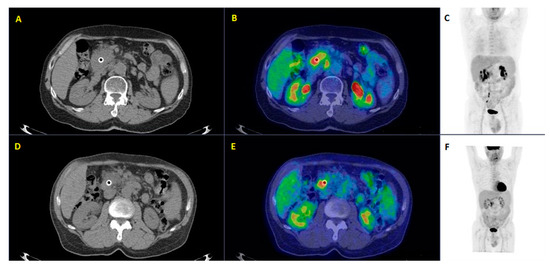

| 7 | Strobel et al. [22] | 2015 | Retrospective study | 50 (64.3) | Preoperative staging biopsy-proven pancreatic adenocarcinoma | The one-stop-shop imaging approach is superior to unenhanced PET/CT in defining the resectability of PDAC, improving the detection of distant metastasis. |